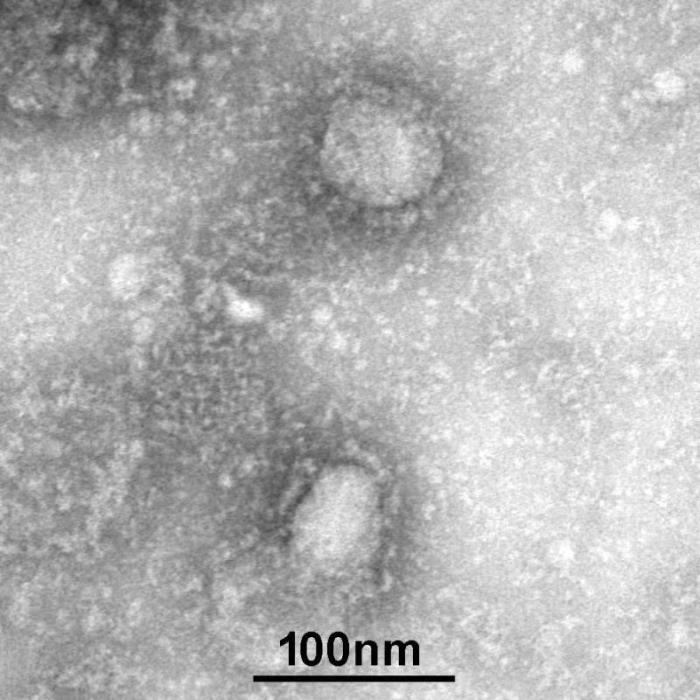

图片来源:中国疾控中心网站

中新网1月24日电 据中国疾控中心网站消息,为做好新型冠状病毒感染的肺炎疫情防控支撑工作,发挥国家病原微生物资源库科技资源共享服务职能,国家病原微生物资源库于1月24日发布了由中国疾病预防控制中心病毒病预防控制所成功分离的我国第一株病毒毒种信息及其电镜照片、新型冠状病毒核酸检测引物和探针序列等国内首次发布的重要权威信息,并提供共享服务。